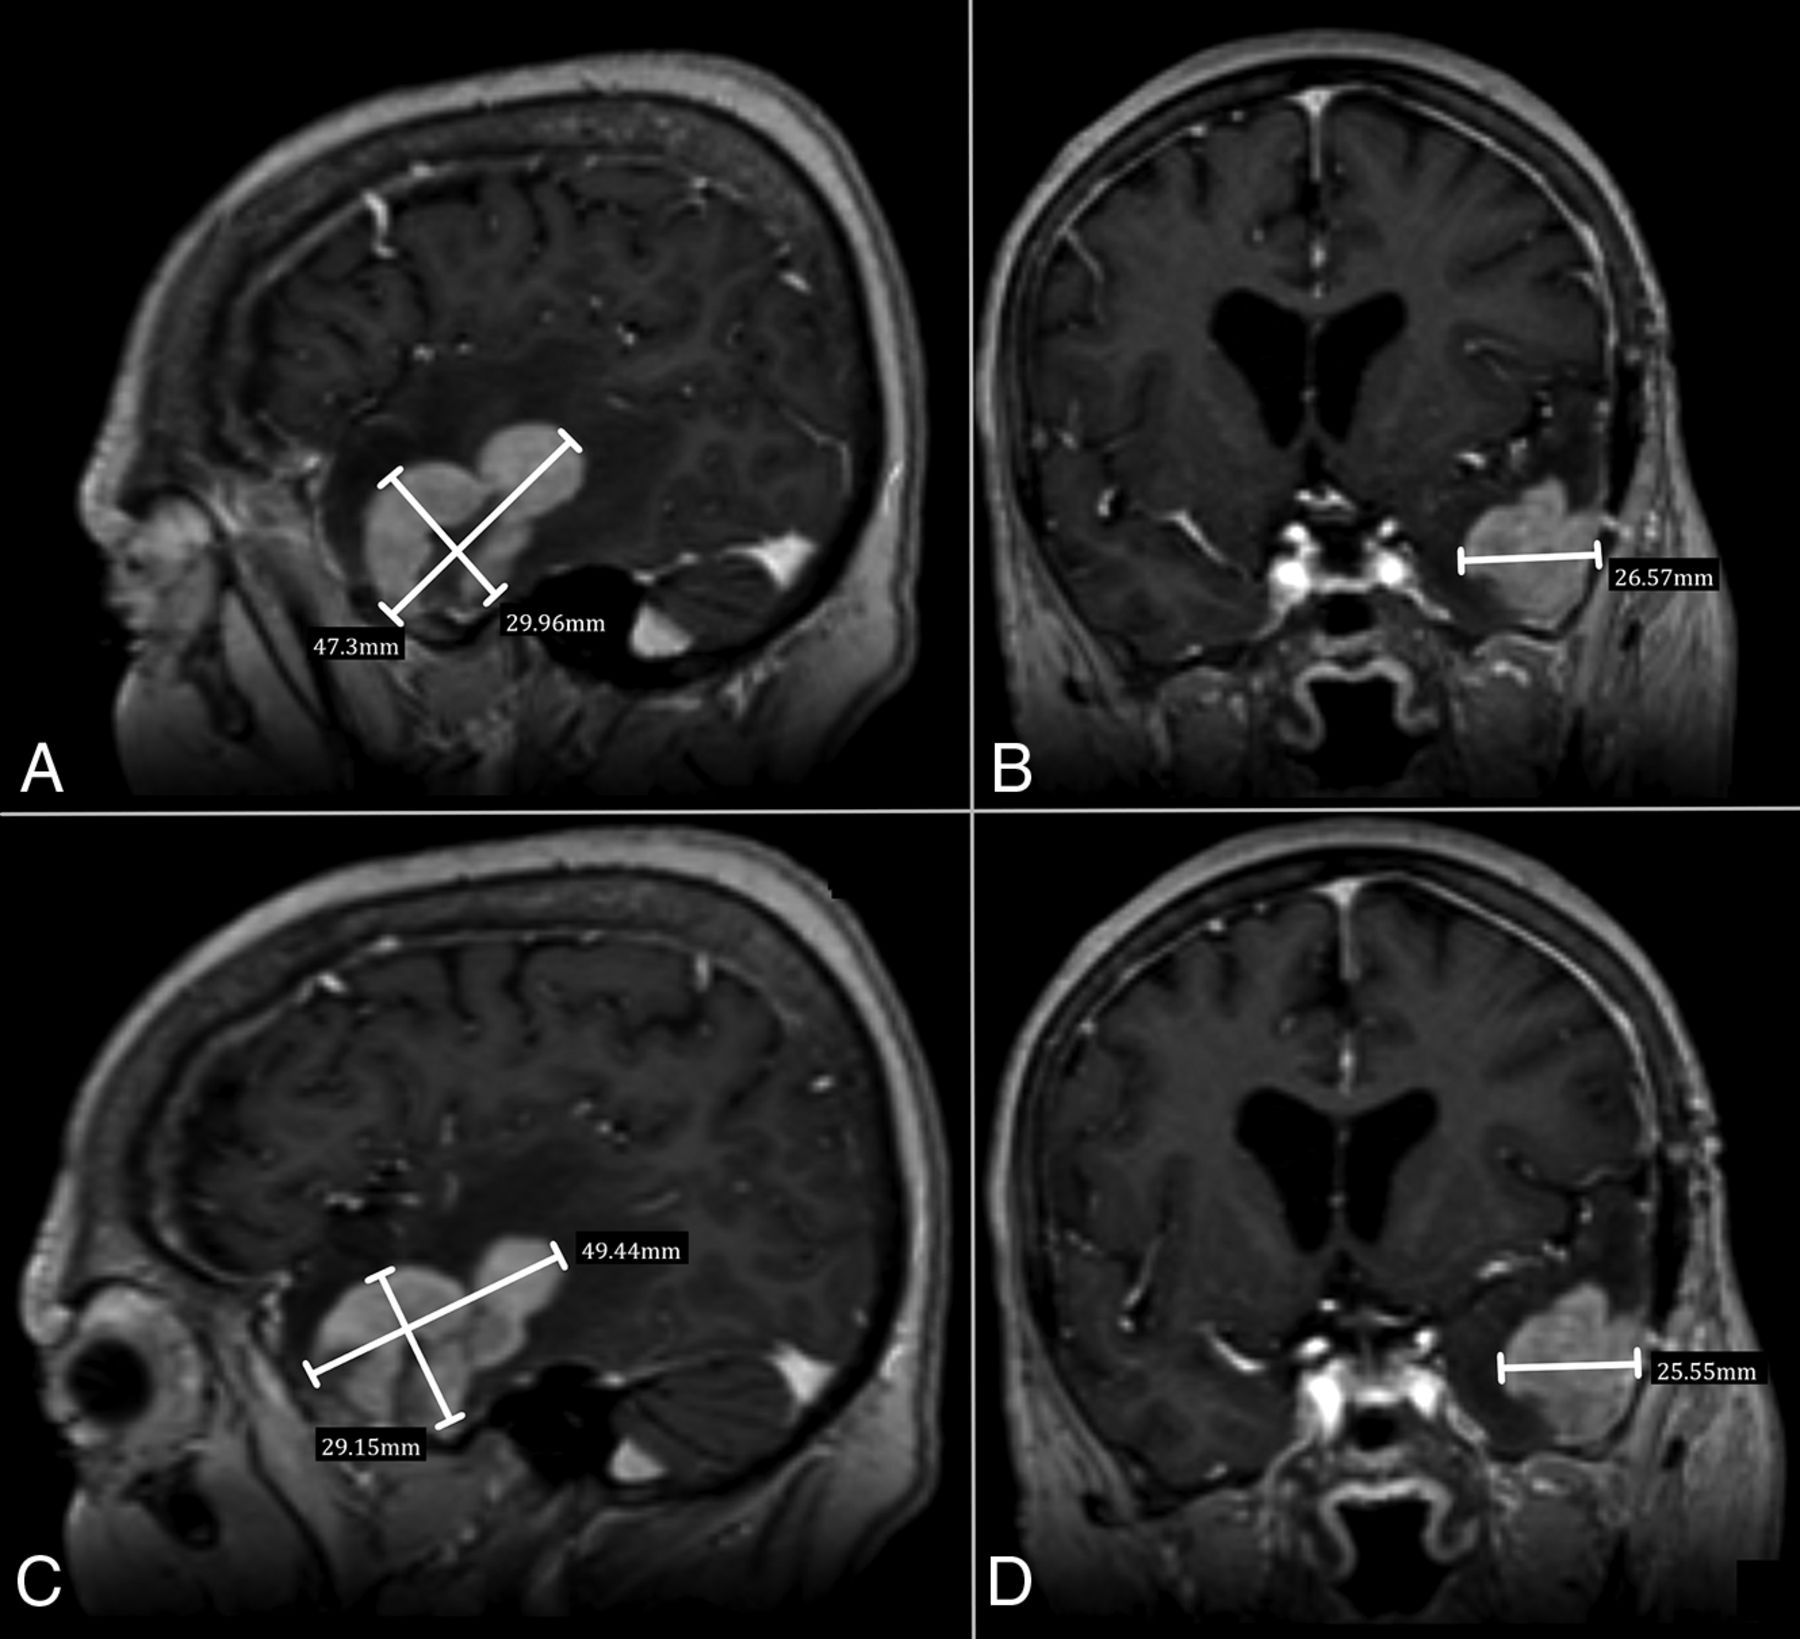

Postcontrast 3D T1 MPRAGE in a 56-year-old woman treated for a left temporal PCNSL. Comparison of the 3D measurements performed by the 2 readers (reader 1, A and B; reader 2, C and D).

Both intra- and interobserver ICCs for 3D, 2D, and longest 1D measurements showed very strong correlations (Table 2). The intraobserver ICC varied from 0.993 to 0.997 in raw units and was calculated to be 0.997 after root manipulation for 2D and 3D measurements. The interobserver ICC varied from 0.967 to 0.992 in raw units and from 0.966 to 0.968 after root manipulation for 2D and 3D, respectively.